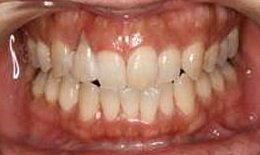

インプラント症例(3)46歳 女性

治療前